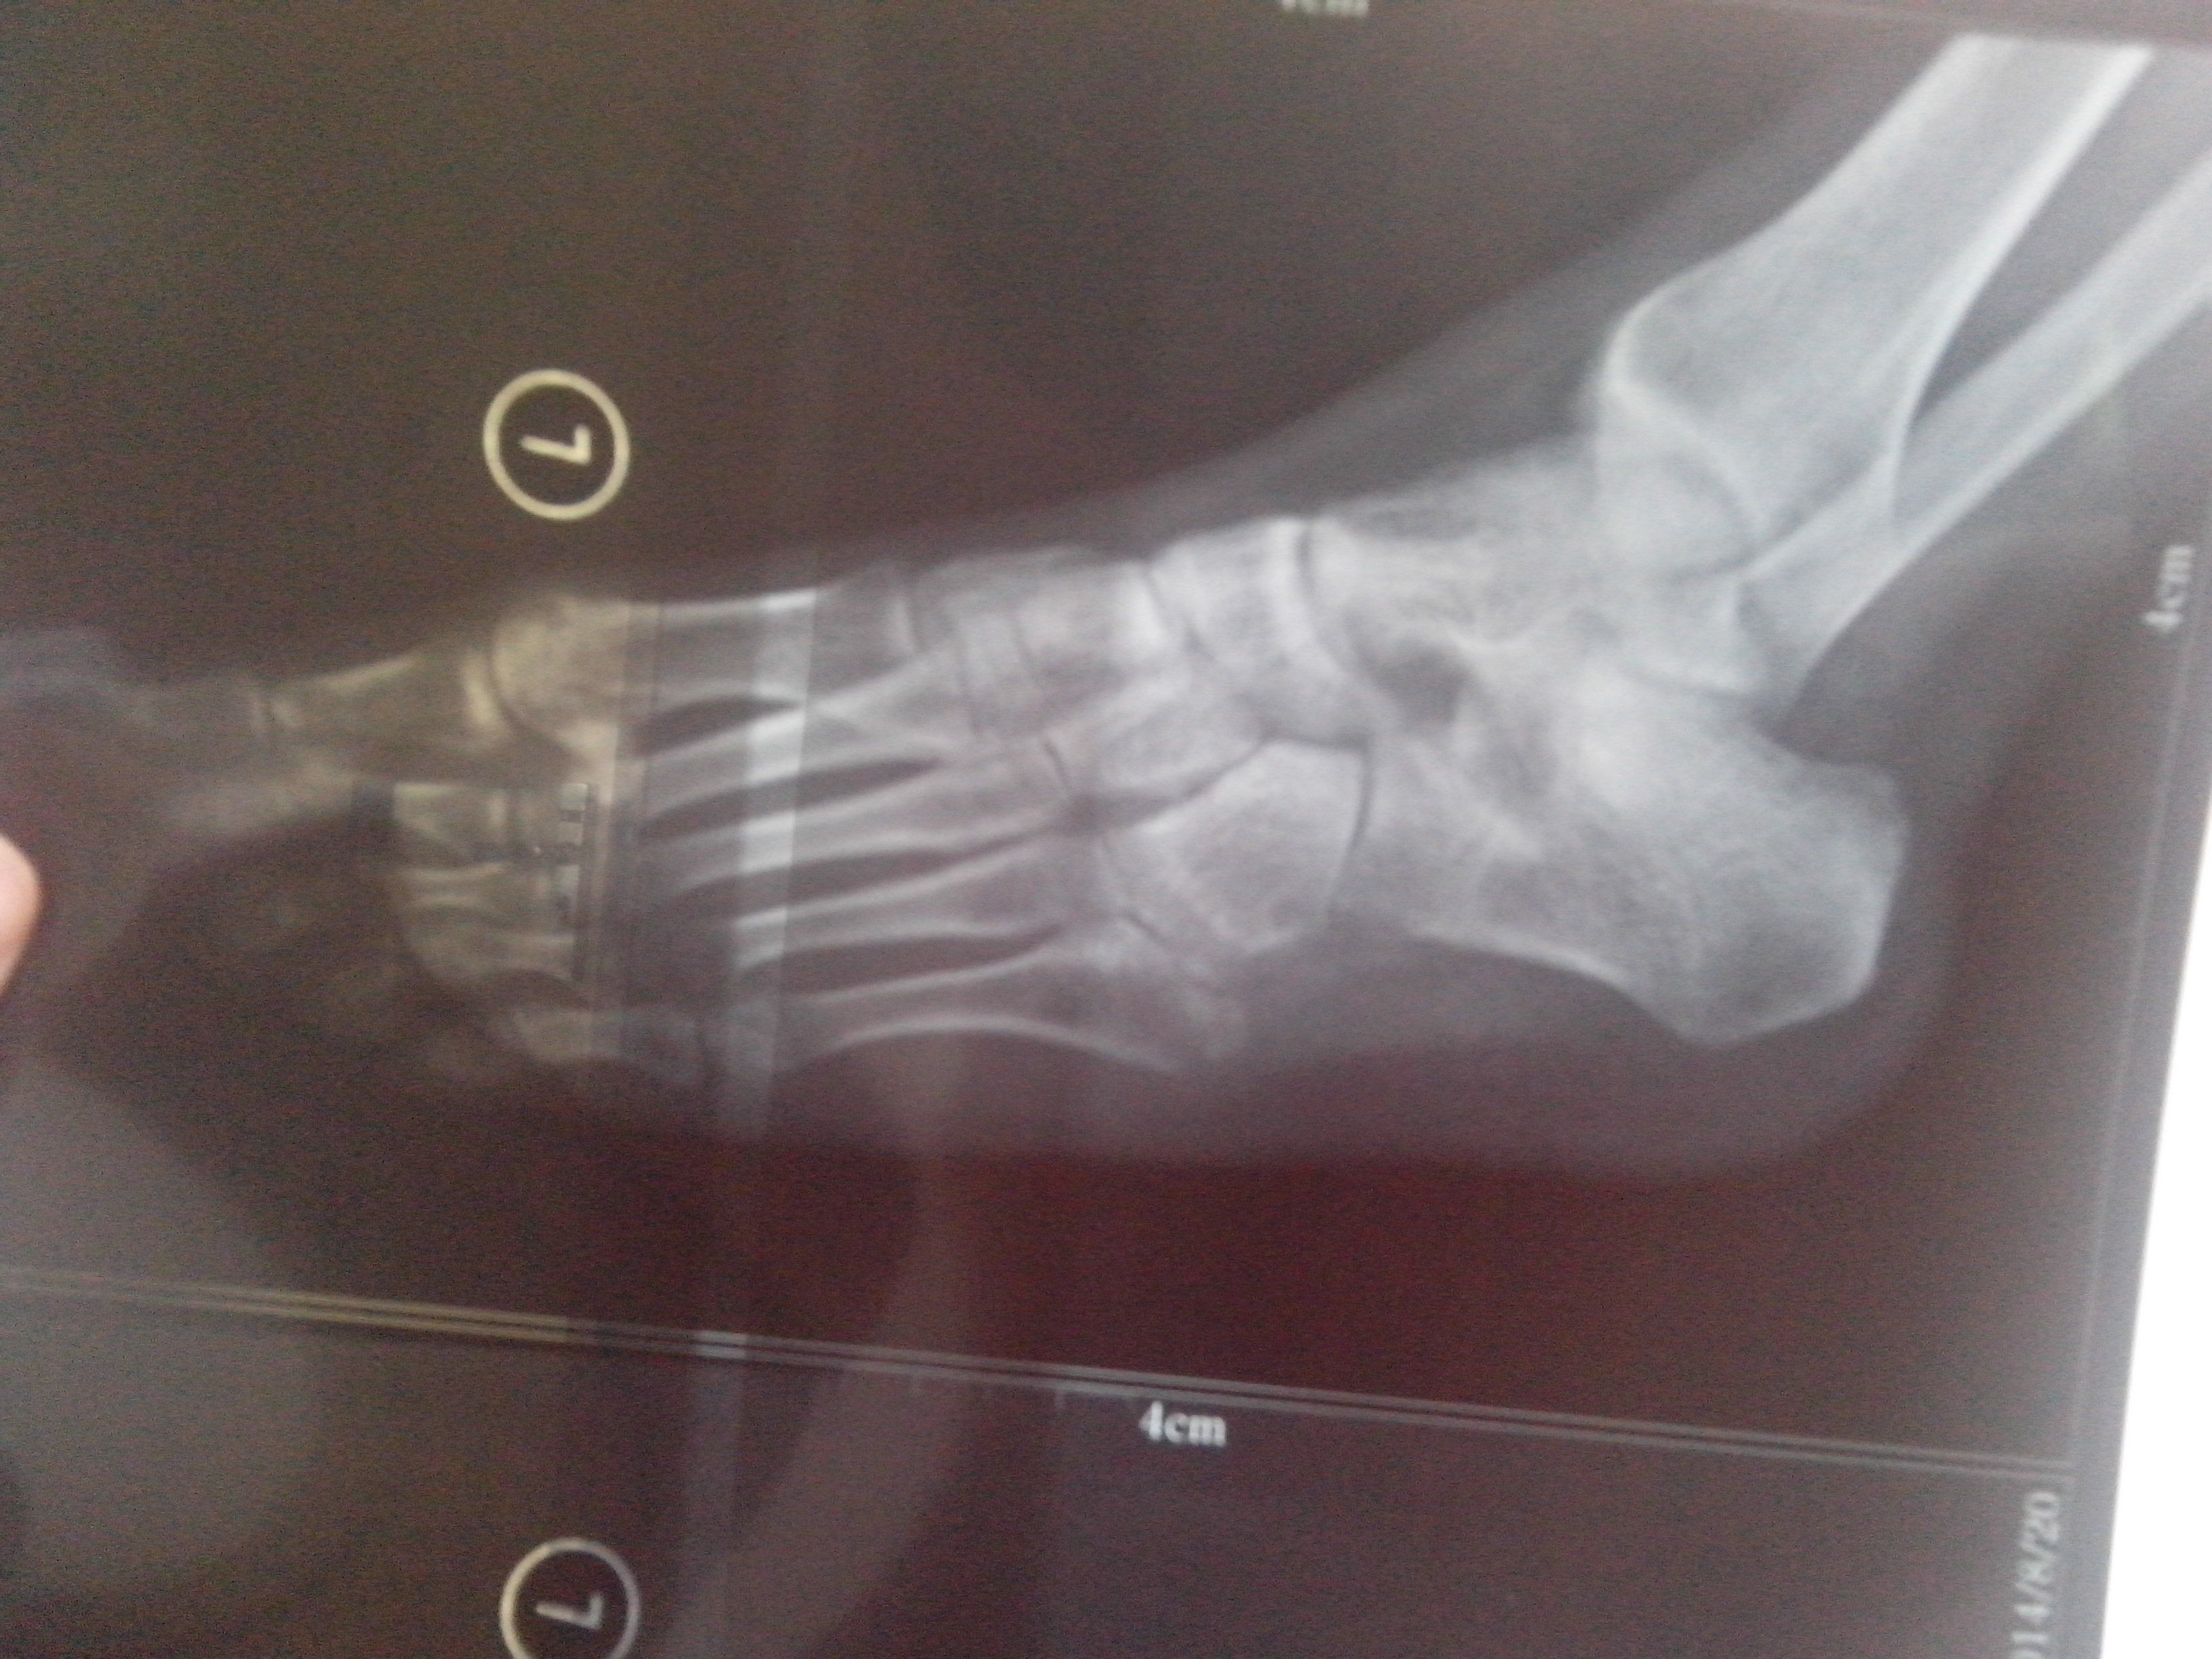

左足第五跖骨骨折,请教一下痊愈方面的问题

这个是人体的脚面吗?求解